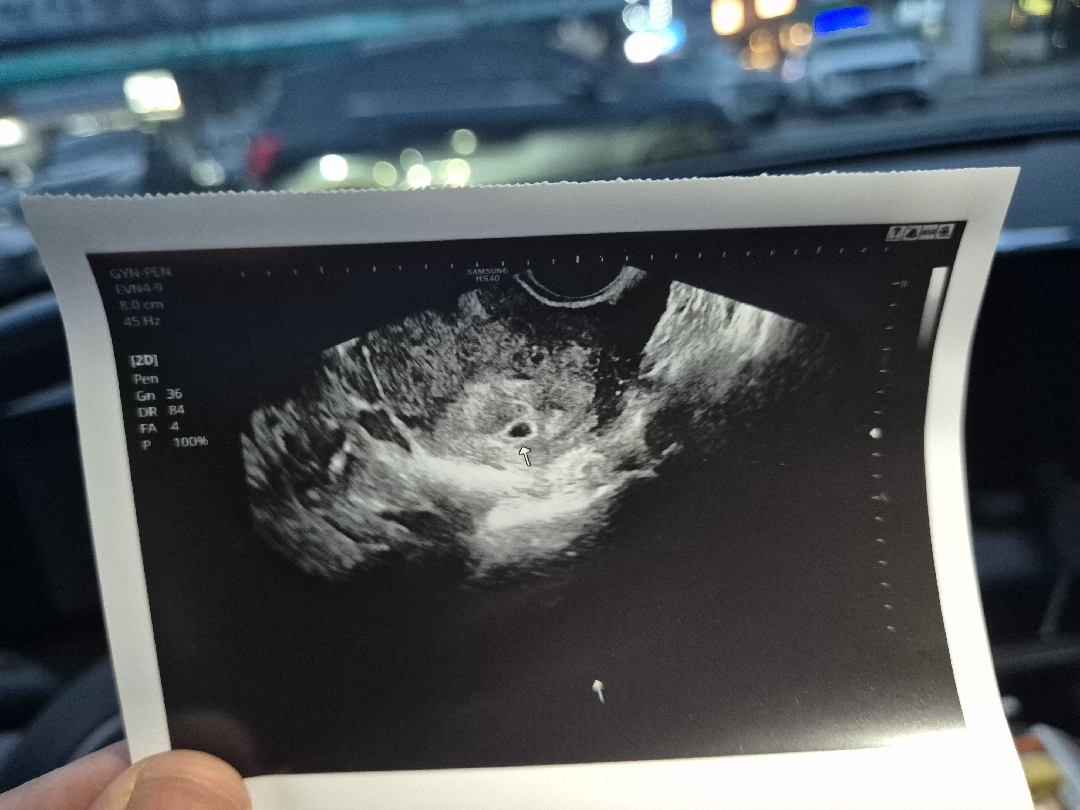

난황 다이아몬드링 보이는것같은데요..?ㅋㅋㅋㅋ 의사쌤이 확대를 너무 안해주셨네요ㅋㅋㅋㅋ

막생기준(8월19일) 5주2일 배란일기준(9월5일 or 6일) 4주6일 아기집집들이 하고왔어요! 쓰리라인임테기 희미하게 보고갔는데 아기집은 사이즈재는의미없다고해서 안재주셨지만 아기집위치나 내막두께는 괜찮다고하시네요😊 4월 자연유산, 7월 화유가 있었어서 아직 걱정이 많지만 이번엔 꼭 우리 베동 다같이 만출🙏🙏 저 작은 아기집안에 뭐가있는거같은데 뭔진 모르겠네요.. 난황은아니겠죠?